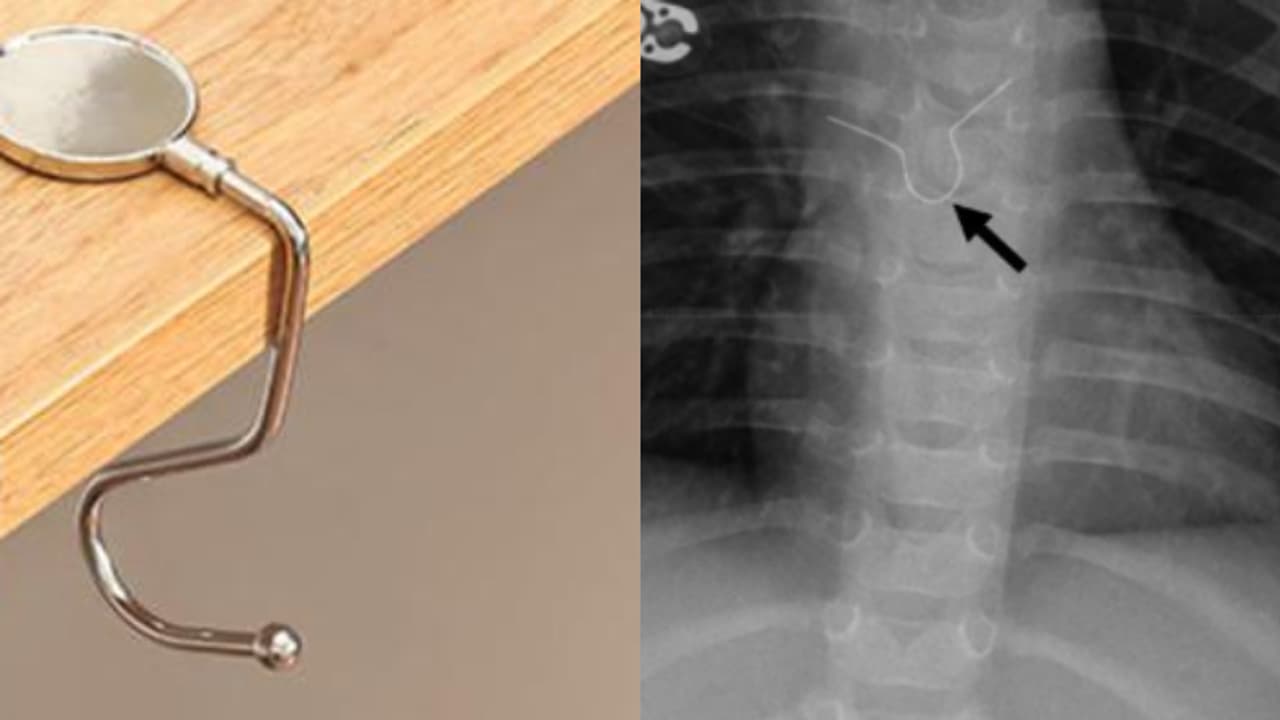

എറണാകുളം: സർക്കാർ മെഡിക്കൽ കോളേജ് ആശുപത്രിയിൽ 15 വയസുകാരന്റെ തൊണ്ടയിൽ കുടുങ്ങിയ ഹാങ്ങർ ഹുക്ക്, എൻഡോസ്കോപ്പി ശസ്ത്രക്രിയയിലൂടെ പുറത്തെടുത്തു. മാർച്ച് 10ന് ആശുപത്രി അത്യാഹിത വിഭാഗത്തിൽ ചികിത്സയ്ക്ക് എത്തിയ ബുദ്ധിപരമായ വെല്ലുവിളി നേരിടുന്ന 15 വയസുകാരന്റെ ജീവനാണ് സങ്കീര്ണ ശസ്ത്രക്രിയയിലൂടെ രക്ഷിച്ചത്.

രണ്ട് ദിവസമായി കുടുങ്ങിയിരുന്ന ഹാങ്ങർ ഹുക്ക് മൂന്ന് മണിക്കൂർ നീണ്ട ശസ്ത്രക്രിയയിലൂടെയാണ് പുറത്തെടുത്തത്. കുട്ടിയുടെ അന്നനാളത്തിൽ സാരമായ ക്ഷതം ഏൽപ്പിച്ച്, ശ്വാസനാളത്തിലും ഞെരുക്കം ഉണ്ടാകാവുന്ന നിലയിൽ ഇരുന്ന ഹുക്ക് എൻഡോസ്കോപ്പിലൂടെ മെറ്റലും, പ്ലാസ്റ്റിക്കും വെവ്വേറെയാക്കിയാണ് പുറത്തെടുത്തത്.